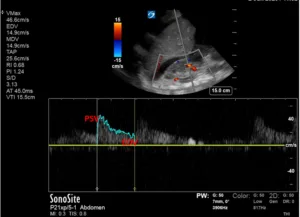

The IVC maximal diameter improved to approximately 2.1 cm, with >50% inspiratory collapse with an estimated right atrial pressure of 8 mmHg (Figure 5). Follow up POCUS after the third session demonstrated further improvement in IVC size (<2 cm), and collapsibility consistent with an estimated right atrial pressure of 3 mmHg (Figure 6). Remarkably, the shape of the IVC shifted from circular to oval during the decongestion of the patient, which is a clinically useful qualitative parameter. Hepatic vein Doppler demonstrated further improvement in S-wave amplitude to near-normal configuration, and the portal vein remained continuous (Figure 7). Intrarenal venous Doppler was not performed, as it is unreliable in ESKD.

Figure 7. POCUS images demonstrating almost equal S and D waves on hepatic vein Doppler and a normal (pulsatility <30%) appearing portal vein waveform.